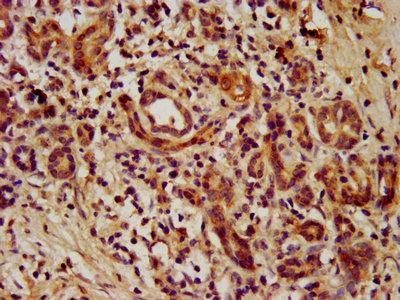

IHC image of CSB-PA860344LA01HU diluted at 1:1000 and staining in paraffin-embedded human colon cancer performed on a Leica BondTM system. After dewaxing and hydration, antigen retrieval was mediated by high pressure in a citrate buffer (pH 6.0). Section was blocked with 10% normal goat serum 30min at RT. Then primary antibody (1% BSA) was incubated at 4°C overnight. The primary is detected by a biotinylated secondary antibody and visualized using an HRP conjugated SP system.

IHC image of CSB-PA860344LA01HU diluted at 1:1000 and staining in paraffin-embedded human pancreatic cancer performed on a Leica BondTM system. After dewaxing and hydration, antigen retrieval was mediated by high pressure in a citrate buffer (pH 6.0). Section was blocked with 10% normal goat serum 30min at RT. Then primary antibody (1% BSA) was incubated at 4°C overnight. The primary is detected by a biotinylated secondary antibody and visualized using an HRP conjugated SP system.